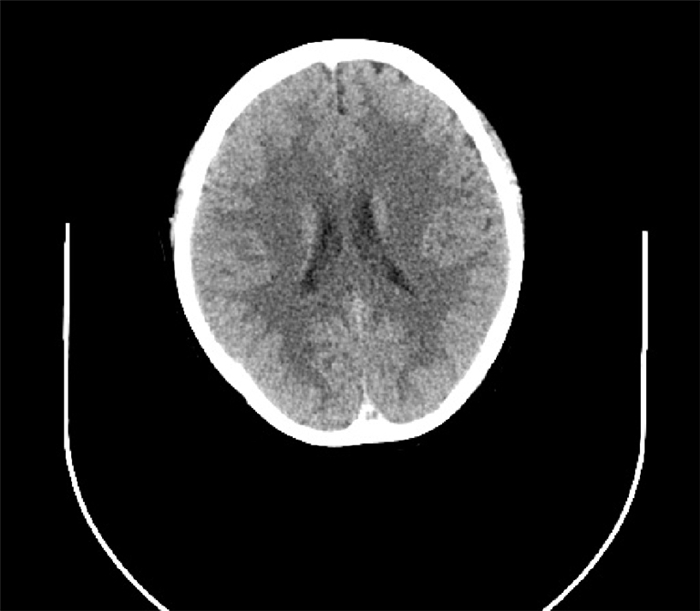

心电图、头部CT血管成像(CTA)和CT平扫均未见异常(图 1、图 2)。

| 图 1 2017年7月9日头部CT平扫未见异常 |